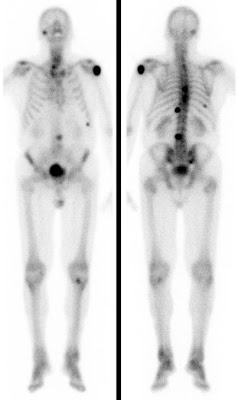

Bei der Skelettszintigraphie werden schwach radioaktiv markierte Phosphatkomplexe verabreicht, die zunächst im Blut durch den Körper zirkulieren und im Verlauf von 2-3 Stunden ausreichend in den Knochen eingebaut werden, so dass dann der Knochenstoffwechsel abgebildet werden kann.

Es bestehen die Möglichkeiten, gleich nach Verabreichung der Phosphatkomplexe die Durchblutung zu untersuchen und auf den Spätaufnahmen den Knochenumbau zu beurteilen. Bei der Skelettszintigraphie gibt es keine Unverträglichkeitsreaktionen auf die verabreichten Radiopharmaka. Im Gegensatz zu vielen Röntgenkontrastmitteln sind die verwendeten Radiopharmaka auch nicht nierenschädlich.

Die Hauptfragestellungen bei der Skelettszintigraphie betreffen die Feststellung evtl. Knochenmetastasen bei Krebserkrankungen und die Unterscheidung von primär entzündlichen vs. primär degenerativen Gelenkerkrankungen, also rheumatischen Grunderkrankungen mit Skelettbeteiligung vs. (aktivierten) Arthrosen.

Darüber hinaus ist die Skelettszintigraphie häufig auch bei der Abklärung unklarer Knochenschmerzen sehr hilfreich, etwa zur Feststellung evtl. Knochentumoren, von Prothesenlockerungen, einer Osteomyelitis, von Frakturen, von Knocheninfarkten etc.